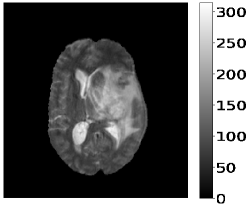

The dataset’s MR images are preprocessed so that the skulls and neck regions are removed. The images are aligned and co-registered to correct any head tilt or mismatches between MR modalities. Each voxel in the image corresponds to of brain tissue. Figure 5 illustrates a 2D axial input MR Images sample and the corresponding ground truth. The input images (a-c) show the different MR modalities: FLAIR, T1CE, and T2 images. The ground truth consists of peritumoral edema (ED) marked in light grey given by an intensity value of , enhancing tumor (ET) represented as a white region with as an intensity value, and the non-enhancing tumor (NET) and necrotic core region (NCR) as dark grey with an intensity value of . The models are evaluated as enhancing tumor (ET), tumor core (TC), and whole tumor (WT). The tumor core corresponds to NET/NCR and the enhancing tumor region. The whole tumor corresponds to all three tumor regions put together. The research aims to learn the ED, NET/NCR, and ET regions.